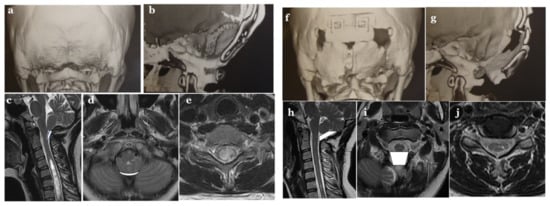

2.3.2. Volumetric Calculations, Morphometric Measurements, and Data Collection

2.4.1. Foramen Magnum Decompression (FMD) for CM-I Type B and CM-Borderline

2.4.2. Expansive Suboccipital Cranioplasty (ECSP) for CM-I Type C

2.4.3. CCF for CM-I with CCJ Instability